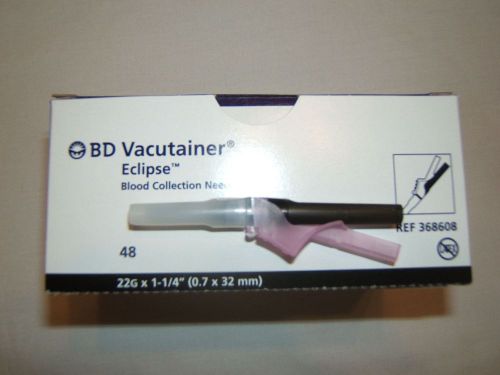

1 NEW BOX SEALED BD VACUTAINER ECLIPSE BLOOD COLLECTION NEEDLE SIZE 22G X 1-1/4"